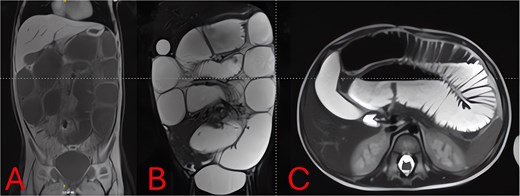

On hospital Day 2, an abdominal MRI without contrast confirmed marked fluid-filled small-bowel loop dilation and a focal transition point in the right lower quadrant (Fig. 3A). Axial sequences demonstrated a periappendiceal fluid collection with mesenteric edema and a possible appendicolith (Fig. 3B). A sagittal plane showed the abscess tracking into the pelvis (Fig. 3C), indicating perforated appendicitis causing adhesive small-bowel obstruction.

MRI of the abdomen—identification of obstruction cause. (A) Coronal T2-weighted MRI showing multiple fluid-filled, dilated small-bowel loops and a focal right lower quadrant transition point. (B) Axial T2-weighted MRI demonstrating a periappendiceal abscess with mesenteric edema compressing adjacent ileal loops. (C) Sagittal MRI view highlighting appendiceal abscess boundaries and a possible appendicolith.

Imaging is critical to distinguish uncomplicated gastroenteritis from mechanical obstruction. While plain radiographs can confirm SBO (Figs 1 and 2), they may not reveal its cause. Although CT offers high sensitivity for appendiceal pathology, radiation exposure is a concern in young children. MRI without contrast provides a reliable alternative, demonstrating excellent diagnostic accuracy for pediatric appendicitis [7]. In our case, T2-weighted images identified a periappendiceal fluid collection, mesenteric edema, and an appendicolith (Fig. 3), guiding prompt surgical intervention.